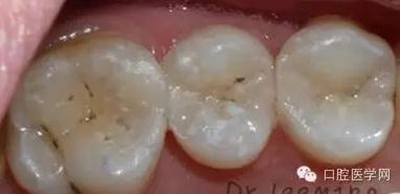

這個患者是我的小粉絲,女兒大部分的齲齒都是我處理好的,家長很滿意。這次媽媽終于有時間來看牙齒,昨天充填了三顆二類洞,術(shù)后照片看,對于第一磨牙最后的充填效果,狠狠的給自己的熱情潑了冷水,第一磨牙窩溝上的齲是沒有處理的,有些覆蓋在上面的樹脂,是因為塑形的時候,把樹脂推過去的,術(shù)后只是調(diào)磨了一下咬合高點,沒有精修和拋光,也打算復(fù)診回來,看看第一磨牙的情況,再選擇重新的充填,然后整體精修拋光。